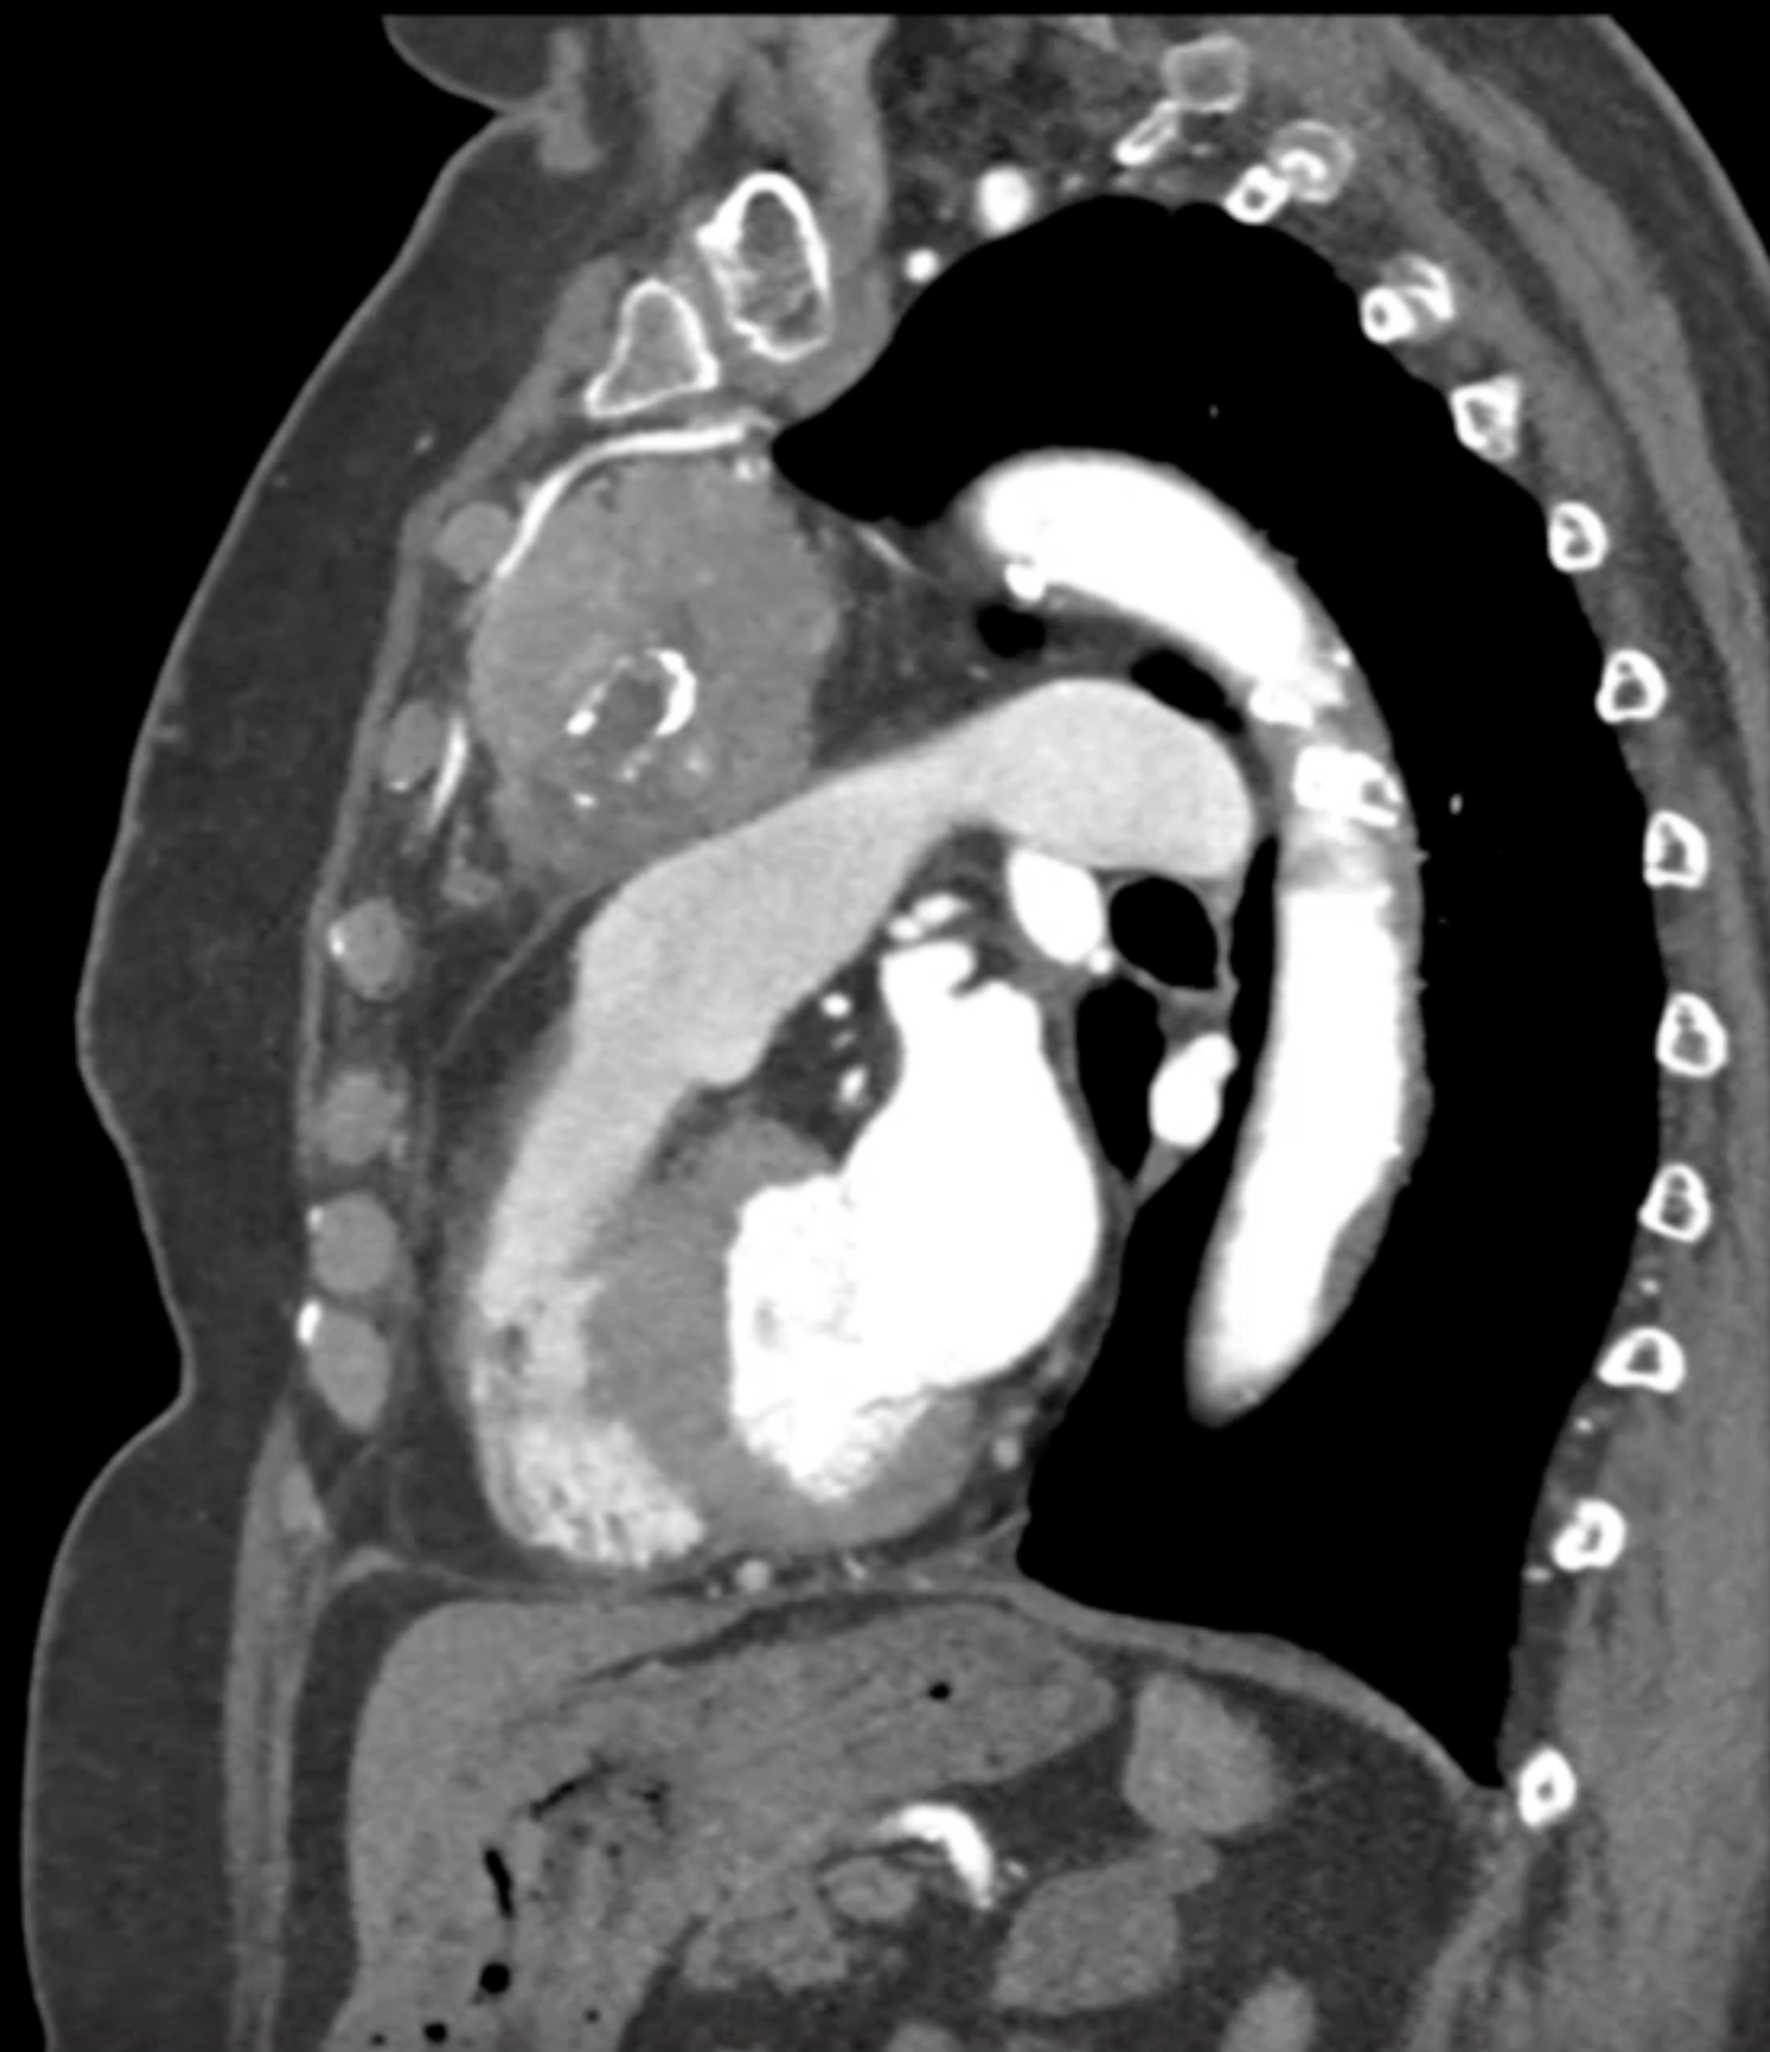

Thymic Carcinoma